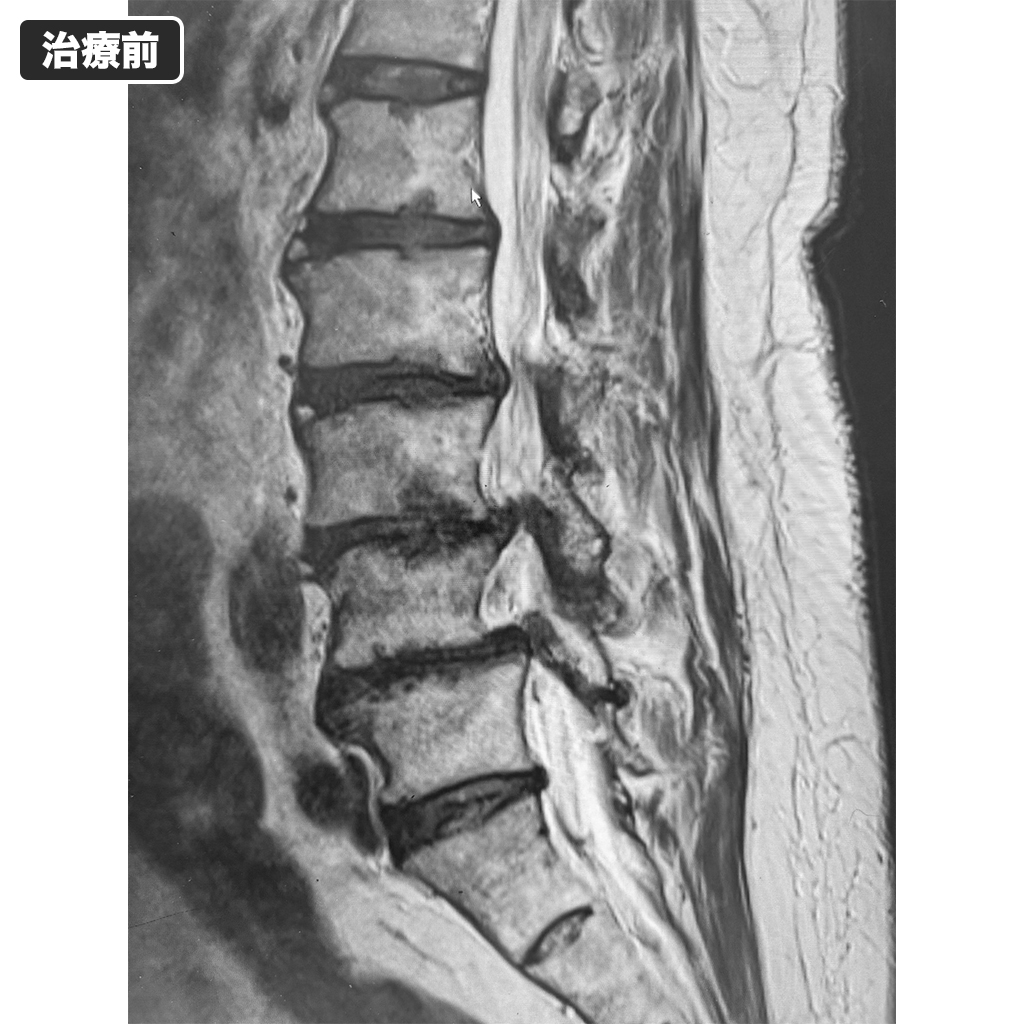

MRI検査

2年6ヵ月前のMRI検査で治療前になります。